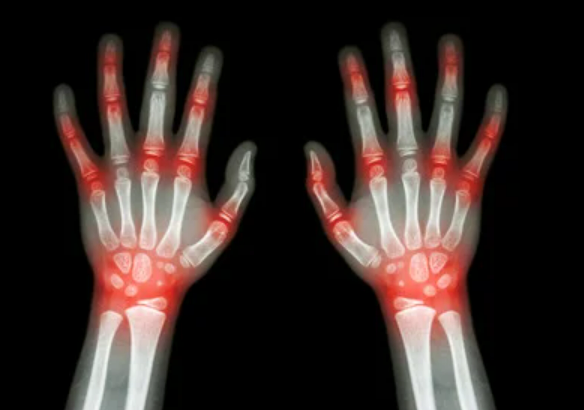

언제고 또 찾아올지 모르는, 바늘로 마디마디를 찌르는 듯한 극심한 고통, 통풍은 몸서리치게 두려운 현대 사회 질병 중 하나입니다. 현대화에 들어서 식습관의 변화에 의해 매년 환자수가 급증하고 있다고 합니다. 바늘 모양의 요산 결정이 관절이나 연부 조직에 쌓이면, 백혈구 세포가 이를 잡아먹다가 풍선이 바늘에 찔리는 형상으로 터지면서 많은 염증물질을 분비하여 빨갛게 붓고 심한 통증이 생깁니다.

극심한 통증과 함께 뼈의 변형을 유발하는 것이 특징이며, 요즘 현대 사회의 성인들에게 자주 나타나는 하나의 질병을 발전했습니다.

통풍 증상을 그대로 참고 방치하게 되면 관절염을 더욱 가속화 시키게 됩니다. 이후 만성 관절염으로 악화될 수 있습니다.